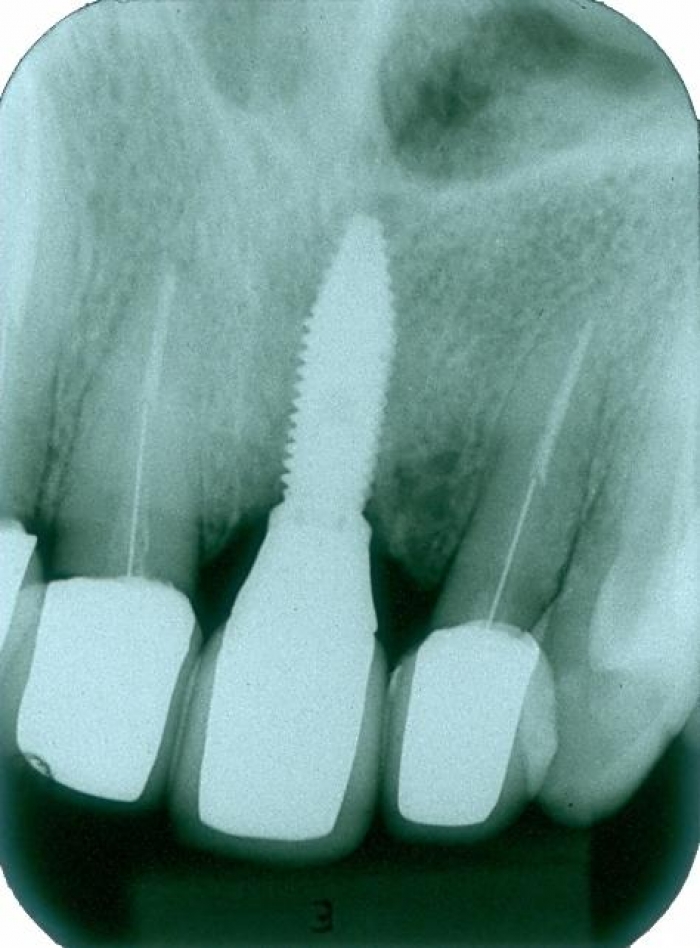

Raio X inicial

Raio X do implante e prótese fixa em porcelana